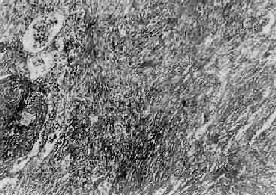

矽肺的基本病变是肺组织内矽结节形成和弥漫性间质纤维化。矽结节是矽肺的特征性病变,结节境界清楚,直径2~5mm,呈圆形或椭圆形,灰白色,质硬,触之有砂样感。随着病变的发展,结节可融合成团块状,在团块的中央,由于缺血、缺氧而发生坏死、液化,形成矽肺性空洞(silicotic cavity)。矽结节的形成过程大致分为三个阶段:①细胞性结节,由吞噬矽尘的巨噬结胞局灶性聚积而成,巨噬细胞间有网状纤维,这是早期的矽结节;②纤维性结节,由纤维母细胞、纤维细胞和胶原纤维构成;③玻璃样结节,玻璃样变从结节中央开始,逐渐向周围发展,往往在发生玻璃样变的结节周围又有新的纤维组织包绕。镜下,典型的矽结节是由呈同心圆状或旋涡状排列的、已发生玻璃样变的胶原纤维构成(图9-22)。结节中央往往可见内膜增厚的血管。用偏光显微镜观察,可以发现沉积在矽结节和肺组织内呈双屈光性的矽尘微粒。除矽结节外,肺内还有不同程度的弥漫性间质纤维化(图9-23),范围可达全肺2/3以上。此外,胸膜也因纤维组织弥漫增生而广泛增厚,在胸壁上也可形成胸膜胼胝,甚至可厚达1~2cm。肺门淋巴结内也有矽结节形成和弥漫性纤维化及钙化,淋巴结因而肿大、变硬。

矽肺

图9-23 矽肺

肺组织呈弥漫性纤维化